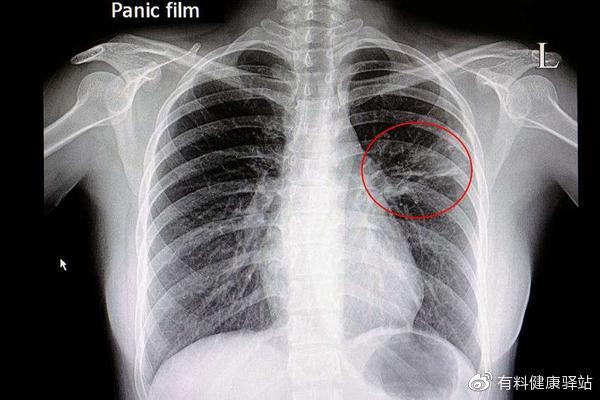

肺炎因为肺部感染,导致原本充满氧气的肺泡被脓液占据,氧气减少,气体交换是比较困难,因此呼吸困难是小儿肺炎的典型表现。

呼吸频率加快的标准为:不到2个月婴儿呼吸次数≥60次/分;2-12个月婴儿≥50次/分;1-5岁幼儿≥40次/分;5岁以上≥30次/分,严重的情况下会出现呼吸清浅,鼻翼两侧扩张迅速,嗜睡、嘴唇发青或者发紫等,一旦出现以上的现象,应该立即送往医院。